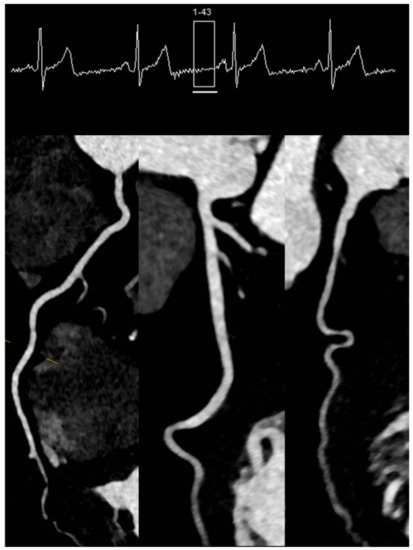

However, as the coronary arteries show reduced movement at end-systole as well, and the systole is less affected by irregularities in heart rate, a “step and shoot” acquisition triggered during the systole often provides excellent image quality (Figure 2). Lastly, the technical advances seen in the last decade have enabled the development of protocols that allow the sampling of data needed for a full characterization of the coronary tree during a single heartbeat. This can be achieved in two ways, depending on the scanner. In scanners that allow a detector coverage of >=16 cm, a complete dataset can be acquired without moving the patient and during a single heartbeat, depending on the heart rate [11][12]. Conversely, with dual-source scanners, an ECG-triggered high pitch “helical” or “spiral” acquisition (a pitch value of ≈3) or so-called “Flash” mode allows for the entire dataset to be sampled in one heartbeat [13][14]. This type of acquisitions offers very high contrast images without “stitching” artefacts with very low radiation exposure for the patient (usually <1 mSv) [10] (Figure 3).

Figure 3. High-pitch dual source spiral protocol (“Flash” mode) in a patient with a stable heart rate of 58/min.